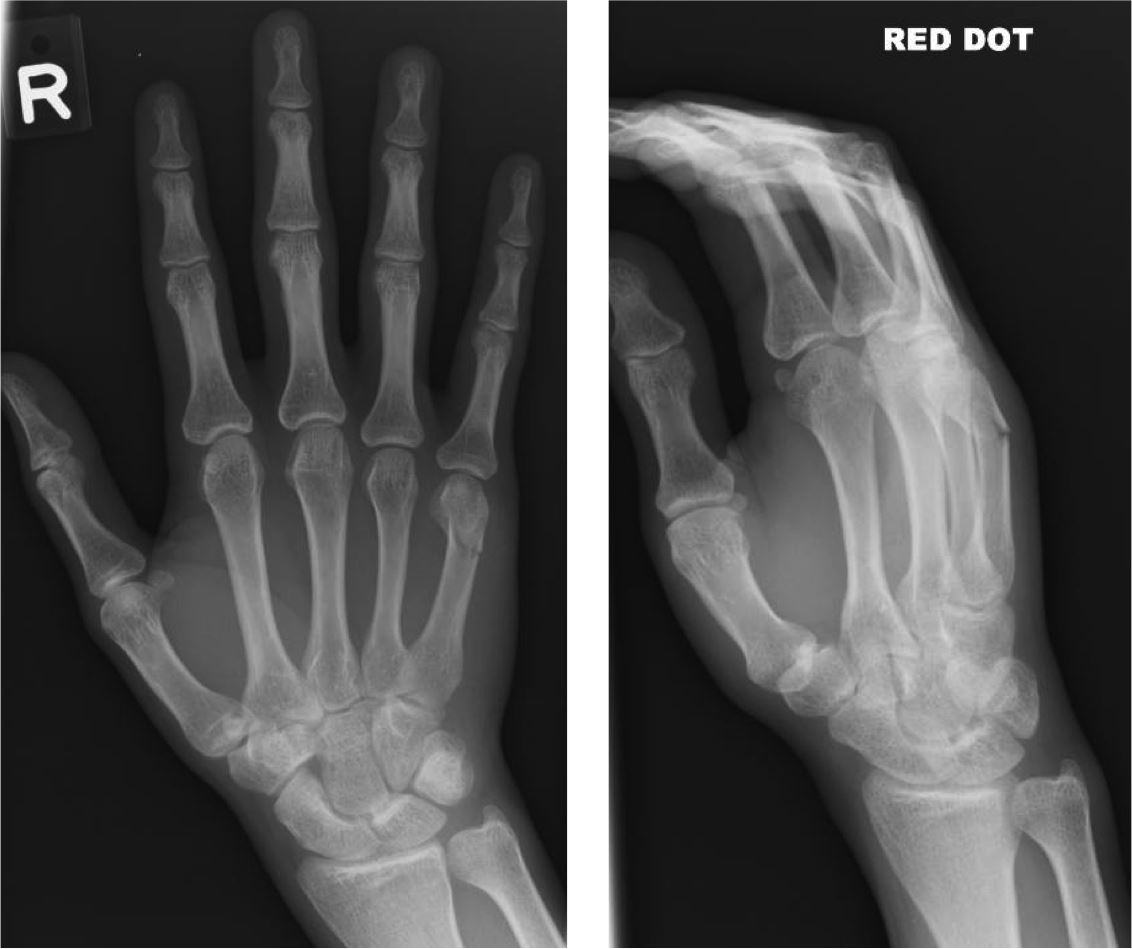

Can you find the fracture?

Q2

Greenstick/ non-displaced fracture of the 5th distal metatarsal

The metatarsal of th elittle finger, a little hard to tell which type of fracture it is at that resolution

A colles fracture of the head of the radius and ulna. Understand exactly what this is here